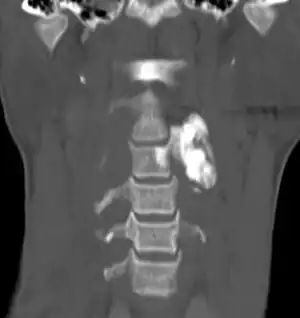

| Osteoblastoma in neck | |

Osteoblastoma is a rare noncancerous bone tumor, of the osteogenic type.[2][3][1] It usually presents with a dull pain in the back.[1]

Generaly, osteoblastomas present between the age of 20 and 40 years.[4] Around 40% are located in the spine, and over half have associated scoliosis.[4]

When diagnosing osteoblastoma, the preliminary radiologic workup should consist of radiography of the site of the patient's pain. However, computed tomography (CT) is often necessary to support clinical and plain radiographic findings suggestive of osteoblastoma and to better define the margins of the lesion for potential surgery. CT scans are best used for the further characterization of the lesion with regard to the presence of a nidus and matrix mineralization. MRI aids in detection of nonspecific reactive marrow and soft tissue edema, and MRI best defines soft tissue extension, although this finding is not typical of osteoblastoma. Bone scintigraphy (bone scan) demonstrates abnormal radiotracer accumulation at the affected site, substantiating clinical suspicion, but this finding is not specific for osteoblastoma.

It usually presents in the vertebral column or long bones.[9][10] The tumors usually involve the posterior elements, and 17% of spinal osteoblastomas are found in the sacrum. The long tubular bones are another common site of involvement, with a lower extremity preponderance. Osteoblastoma of the long tubular bones is often diaphyseal, and fewer are located in the metaphysis. Epiphyseal involvement is extremely rare. Although other sites are rarely affected, several bones in the abdomen and extremities have been reported as sites of osteoblastoma tumors.